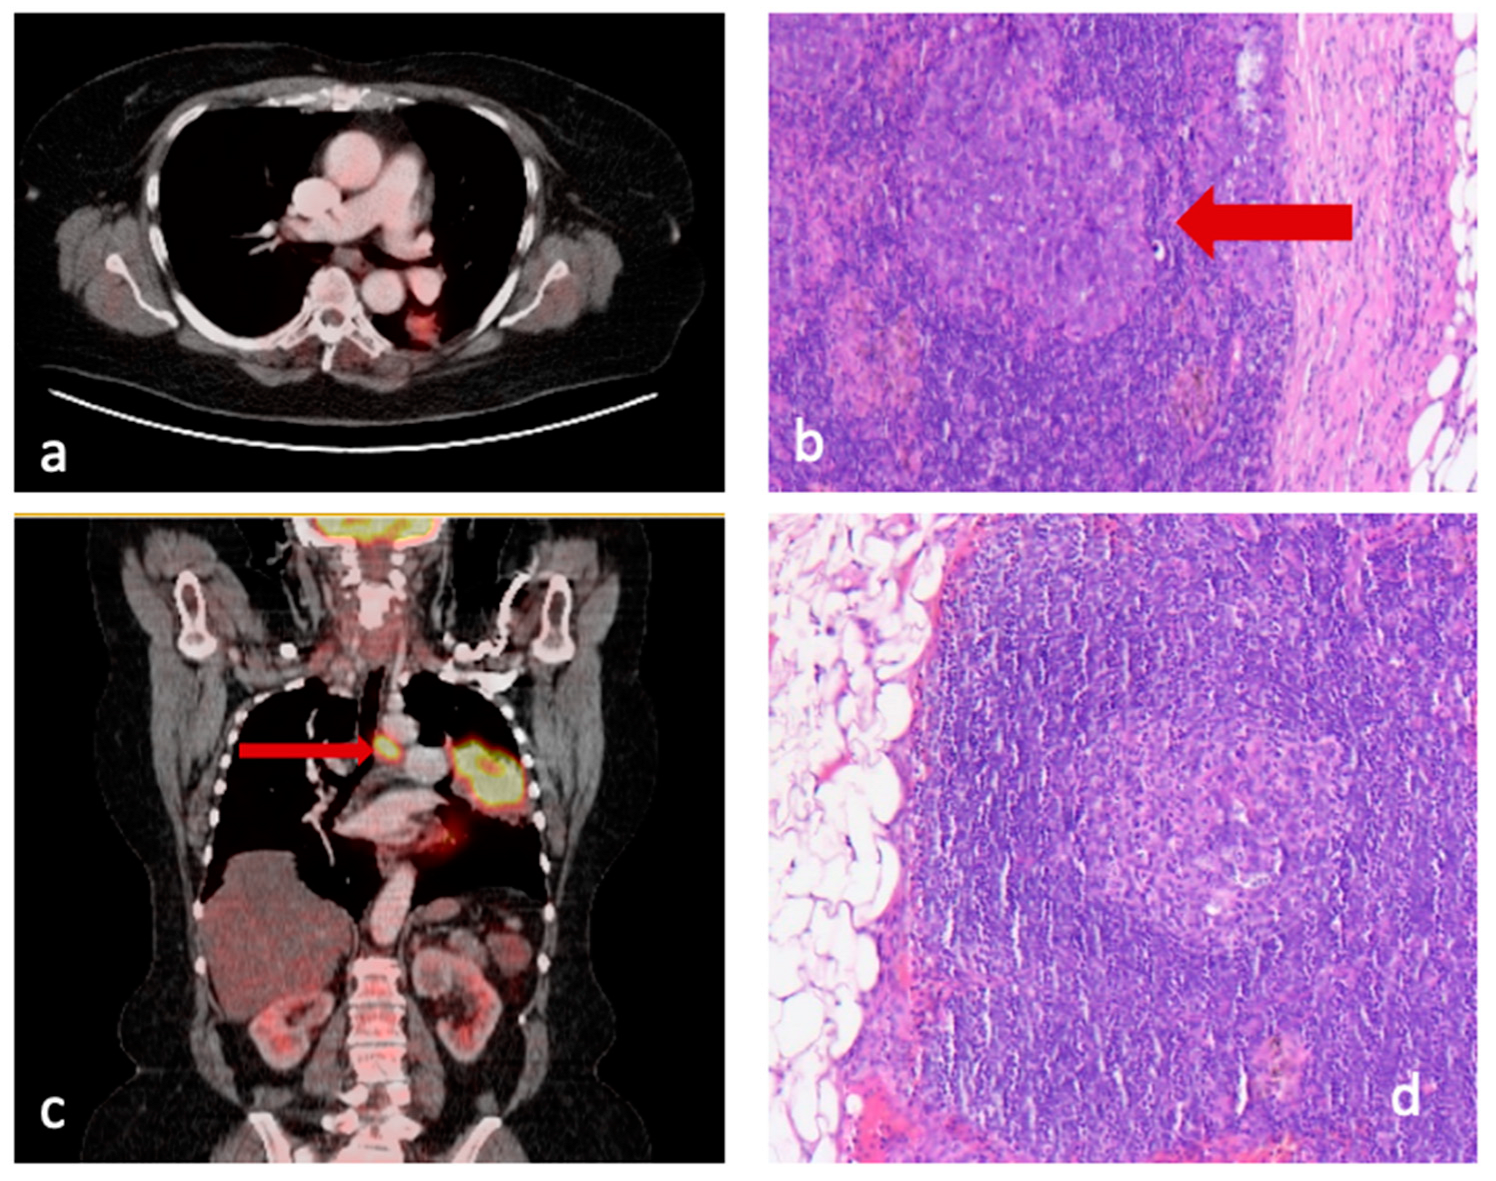

- Group 1 included patients with pathologically confirmed lymph node involvement. Subgroup 1.1 showed no discrepancy between presumed pre- and confirmed postoperative lymph node involvement, whereas subgroup 1.2 patients were PET-negative but had pathologically positive lymph nodes (false negative, Figure 1a,b).

- Group 2 consisted of patients with no pathological detection of infiltrated lymph nodes. Subgroup 2.1 showed no discrepancy, but subgroup 2.2. included patients with suspected increased glucose uptake on PET/CT (indicating preoperatively presumed lymph node involvement) but without histopathological confirmation (false positive, Figure 1b,c).